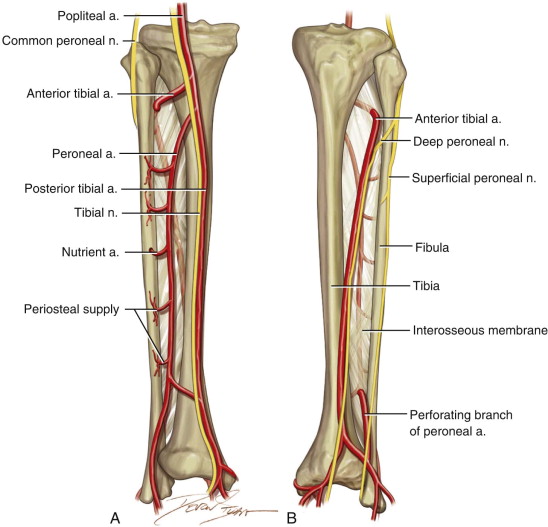

The lower limb | Basicmedical Key

Common Fibular Nerve Anatomy – pediagenosis

Nerves Leg Diagram – koibana.info | Nerves in leg, Muscle anatomy …